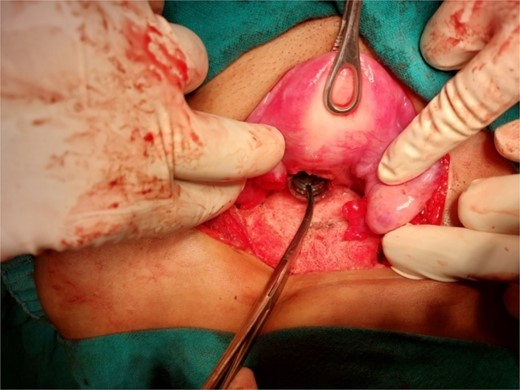

A 26-year-old nulliparous lady from a rural area was referred to emergency from a primary health care centre with a failed attempt to remove an impacted uterine foreign body. On per speculum examination, an impacted hard pipe-like structure was protruding from the cervix. The patient gave a history of foreign body insertion 9 years back, however, failed to provide a detailed account of the mode of insertion or history of sexual assault. She went to seek medical care only after developing profuse foul-smelling discharge and chronic pelvic pain. Removal was attempted under local anaesthesia but failed. Transvaginal scan showed a bulky uterus with an apparently normal endometrial thickness and echotexture; however, the cervical canal was distended with an echogenic area and areas of calcification (Figs 1 and 2). She was taken up for removal of the foreign body under general anaesthesia. As a hard pipe-like structure was already protruding, removal was tried by grasping it with a Kocher’s forceps. After multiple attempts part of the foreign body was removed. Hysteroscopy showed that the lower endocervical canal was clear and a ring-like structure occupied the upper endocervical canal. Removal under direct vision using a hysteroscopic grasper was attempted but failed due to the impaction and size of the object and the hysteroscope could not be negotiated beyond the object. A laparotomy was performed and after an assessment of anatomy and tactile sensation to assess accessibility, incision on the posterior surface of the uterus was given (Figs 3 and 4) and the object was removed (Fig. 5). The incision was closed in two layers. Intercede was placed at the repair site. An extended course of antibiotics was given for 7 days. Post-operative recovery was uneventful. Contraception for at least 1 year, the need for proper antenatal care, the risk of rupture, and mandatory caesarean delivery were counselled to the couple.

Laparotomy revealing the nozzle head in the lower uterine cavity.